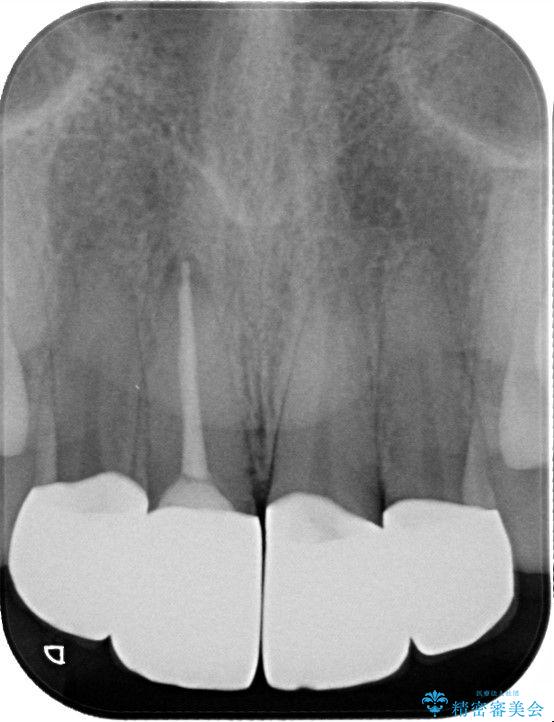

- 他院で治療した前歯の色が気になるということで来院された患者様です。前歯に色の差があり、レントゲンから内部にう蝕も見られたため、審美性に優れ、う蝕になりにくいオールセラミッククラウンで治療いたしました。